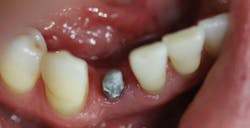

This patient presented with discomfort and mobile teeth Nos. 24 and 25. Extractions were performed, and the area was allowed to heal for six months. Mini-implants were placed in site Nos. 24 and 25 and immediately loaded with temporary crowns. The final splinted restoration was cemented two weeks later.

Figure 8: Initial implant placement DIO 3.0 x 16 mm implants

Figure 9: Implants restored two weeks after placement